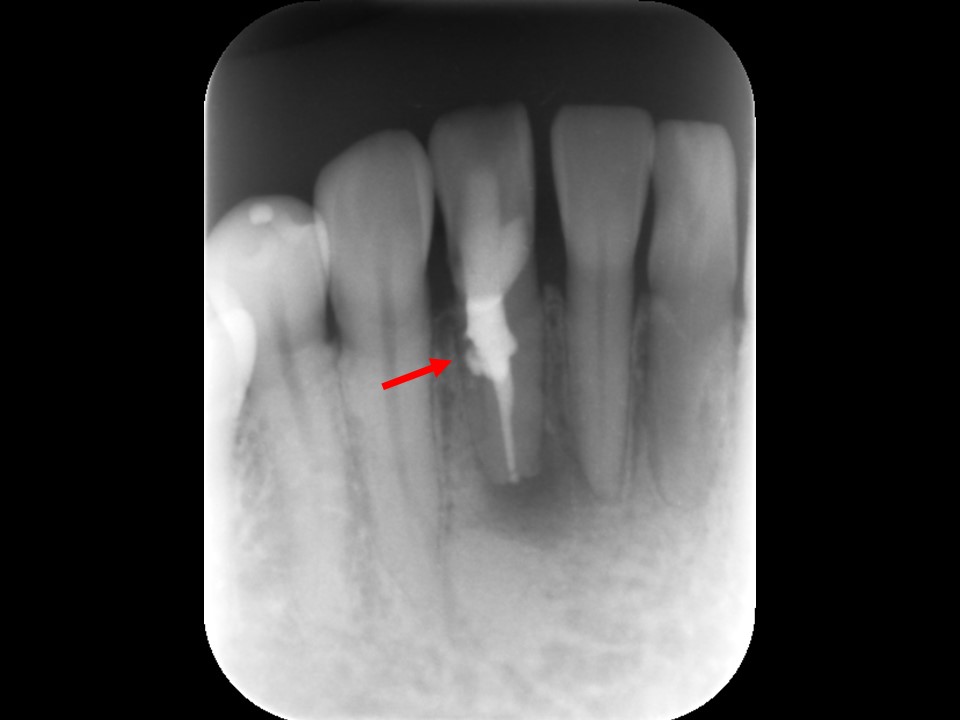

根管充填および歯冠修復処置

症状が無くなり、マイクロスコープで根管内部がきれいになったことを確認できたため、根管充填を行いました。

バイオセラミックシーラーとガッタパーチャにてパーフォレーションの真下まで隙間なくお薬を詰めました。パーフォレーション部から上方はバイオセラミックセメント(RRM)を充填してリペアを行い、根管治療が終了しました(下写真)。根管治療後は、コンポジットレジンによるダイレクトボンディングにて歯冠修復処置を行いました。

根管充填後のレントゲン画像です。パーフォレーション部にバイオセラミックセメントが充填されているのが分かります(赤矢印)。

予後確認

定期検診時、適宜レントゲンやCTにて根尖病変の治癒の程度を確認します。(下写真)

根管治療7か月後のレントゲン画像です。根尖病変はきれいに治癒し、骨の再生を認めます(黄矢印)。パーフォレーション部も骨吸収は認めず、予後は非常に良好です。